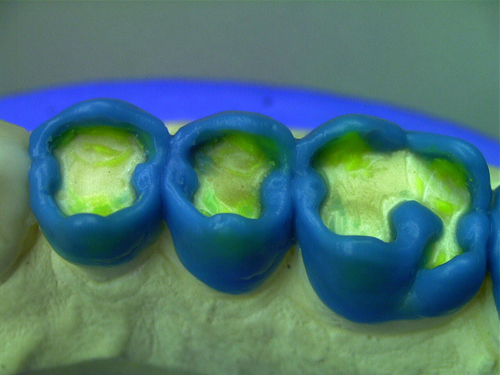

ABSTRACT El Bruxismo es una entidad patológica en la que concurren diferentes factores. Entre ellos el stress que conlleva consigo la vida moderna, constituye el Factor Predisponente sobre el que se ha abundado en innumerables tratamientos de tipo general, actuando sobre la psiquis y el comportamiento del individuo, ya sea con fármacos o bien mediante medios psicológicos. Sin embargo, como tantos desequilibrios provocados por el stress, confluyen siempre con un Factor Desencadenante, que en el caso del Bruxismo se encuentra en las desarmonías entre los componentes varios del Sistema Estomatognático. DESARROLLO Paciente varón, de 43 años, constitución atlética. A la inspección se observan desgastes oclusales que alcanzan la calidad de Facetas Parafuncionales, con dentina expuesta y empastes totalmente gastados y evidentes signos de falta de Disclusión Canina de ambos lados. Sobre dicho montaje se realiza un Encerado Progresivo de Diagnóstico, aportando en el mismo los elementos necesarios para obtener todos los principios básicos de una Oclusión Orgánica. FIG. 6 a 24 Una vez aprobado el fisiologismo de la oclusión en el articulador, se reproducen modelos de yeso con la nueva situación, y se estampa un SET UP en cada maxilar. FIG. 25/26 Procedemos entonces al tallado de las piezas correspondientes a la Guía Anterior, y rebasamos los estampados, creando en boca una nueva situación desoclusiva, que permanece en boca durante los pocos días que transcurren entre la primera y segunda visita de trabajo. FIG. 27/33 Ya abordando en esta segunda visita los sectores posteriores, tanto superiores como inferiores, tallamos siempre de manera supragingival, destacando la importancia vital de la forma obtenida en las provisionales, a las que abrimos plenamente las troneras para lograr una correcta higiene. FIG.34 a 43 FIG. 44 a 52 Efectuados los colados en oro y probados en boca, en el laboratorio se confecciona el bizcochado de la nueva Guía Anterior, la que puede o no copiarse de la Guía Anterior provisional, mediante la técnica denominada Trayectoria Funcionalmente Generada, que consiste en realizar en la platina del articulador un registro estereográfico sobre acrílico Duralay en polimerización. FIG. 57/58 Ajustados todos los detalles mediante esta técnica, se instala en boca en forma Provisional y se deja funcionando una semana o dos, al cabo de las cuales se chequean las disclusiones , los ajustes, la eficacia masticatoria, la carencia de sintomatología articular y muscular. FIG.59 a 63 PIE DE FOTO FIG.9 OBTENCIÓN DE LA GUÍA ANTERIOR FIG.10 Y 11 PITOMBOS. ALINEAC. TRIDIMENSIONAL FIG.12 PITOMBOS. DISCLUSIÓN DER. FIG.13 PITOMBOS. DISCLUSIÓN IZQ. FIG.14 WILSON INF. FIG.15 WILSON SUP. FIG.16 BOCA DE PEZ INF. FIG.17 BOCA DE PEZ SUP. FIG.18 VISTA OCLUSAL FIG.19 O.R.C. FIG.20 DISCLUSIÓN DERECHA FIG.21 CRESTAS TRIANG. INT. FIG.22 CRESTAS TRIANG. INT. FIG.23 CRESTAS TRIANG. INT. FIG 24 CRESTAS TRIANG. INT. FIG.59 DISCLUSIÓN IZQ. FIG.60 DISCLUSION IZQ. FIG.61 DISCLUSIÓN DER. FIG.62 DISCLUSION DER. FIG. 63 AJUSTE PERIFÉRICO